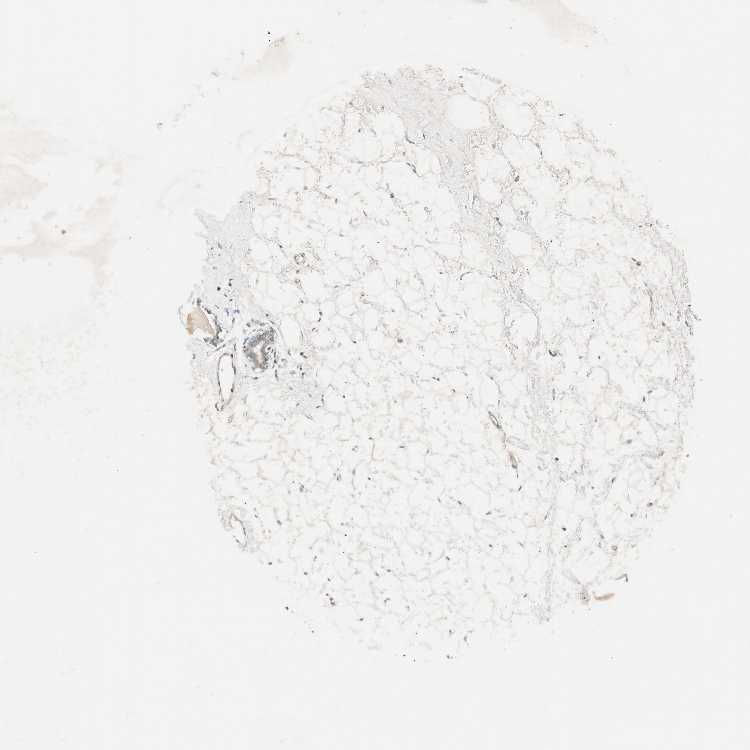

BREAST - Antibody stainingi

Antibody staining in the annotated cell types in the current human tissue is reported as not detected, low, medium, or high, based on conventional immunohistochemistry profiling in selected tissues. This score is based on the combination of the staining intensity and fraction of stained cells.

Each image is clickable and will lead to virtual microscopy that enables deeper exploration of all samples and also displays staining intensity scores, fraction scores and subcellular localization as well as patient and tissue information for each sample.

Antibody HPA003750

Adipocytes Not detected

Glandular cells Low

Myoepithelial cells Low